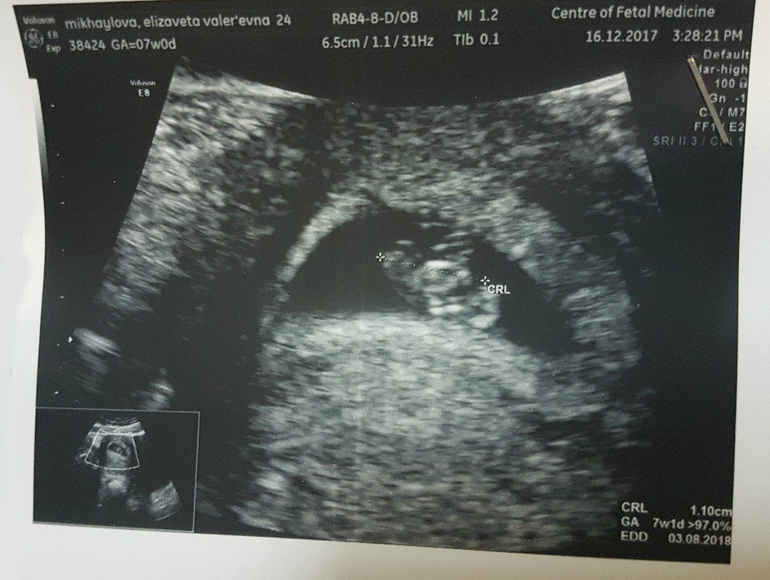

первое УЗИ :)

УЗИ, КТГ, доплерСходили в первый раз на УЗИ вчера, срок был ровно 7 недель. Все хорошо, соответствуем сроку))) Желточный мешочек 2,9 мм, эмбриончик 11 мм, сердцебиение 150 уд./мин (это не мало? читаю у всех 160-170). По передней стенке матки закрепился.